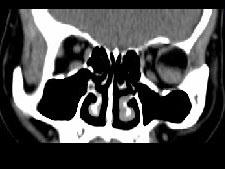

女,52岁,左眼球突出二十余年,T、T均正常,影像检查如图所示,应诊断为()A.错构瘤B.脂肪瘤C.畸胎瘤D.血管瘤E.炎性假瘤

问题 女,52岁,左眼球突出二十余年,T、T均正常,影像检查如图所示,应诊断为()

选项 A.错构瘤 B.脂肪瘤 C.畸胎瘤 D.血管瘤 E.炎性假瘤

答案 A